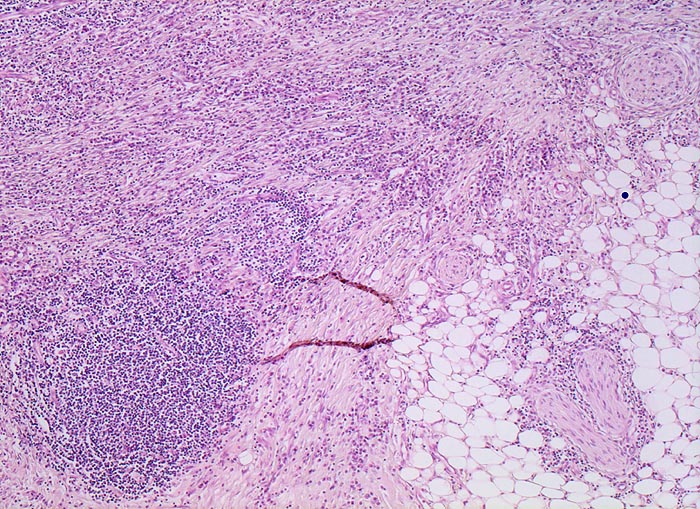

• Transmurale Entzündungsinfiltrate mit Lymphfollikelbildung.

• Zahlreiche epitheloid-riesenzellige Granulome in allen Wandschichten.

• Schlitzförmige fissurale Ulzera mit Vernarbung der umgebenden Submukosa.